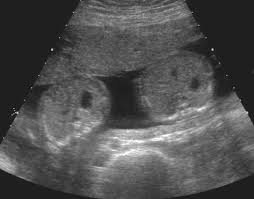

The diagnosis of the Fetus Papyraceus seldom during pregnancy. In the case of twin pregnancies, if one twin vanishes, then it is speculated to be the Fetus Papyraceus or Twin vanishing syndrome. The Fetus Papyraceus is incidentally diagnosed during the are ultrasonography. Mostly the Fetus Papyraceusis found during childbirth. There is no special medical treatment for the Fetus Papyraceus.